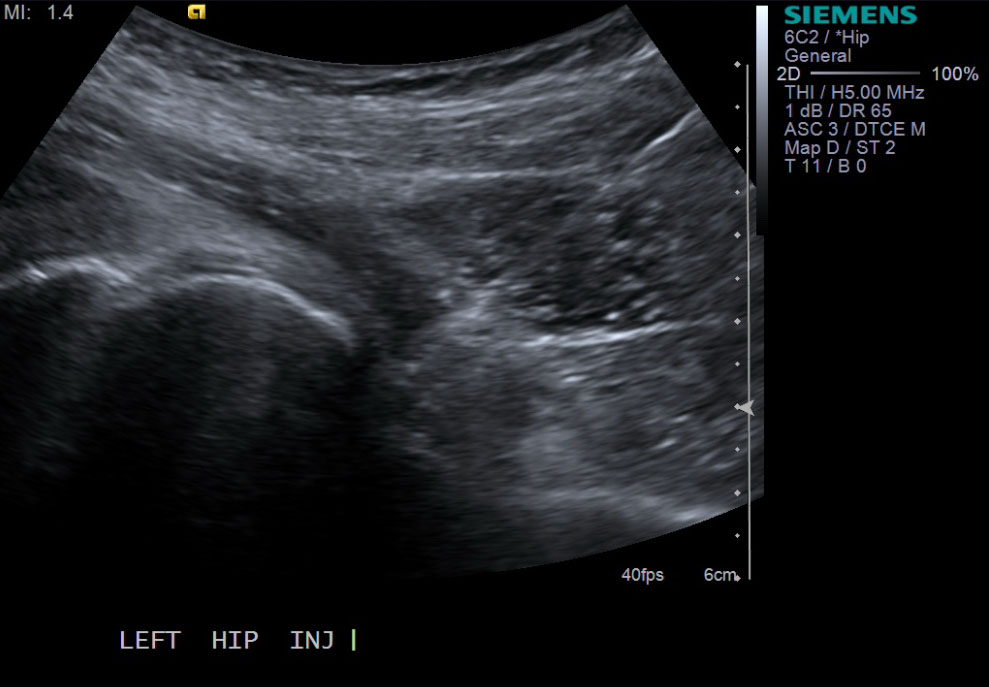

• probe: 6Mhz curved probe

3. Scan longitudinally along the axis of the femoral neck. Target the femoral head and neck junction and look for the overlying joint capsule. Scan plane should be lateral to the femoral vessels.

10.Advance needle with ultrasound guidance to the level of the femoral head and neck junction.

• 11. Test inject to see if easy flow with 1% lidocaine. If no resistance and see distention of the joint capsule, exchange for 5cc syringe with injectable steroid and ropivacaine.